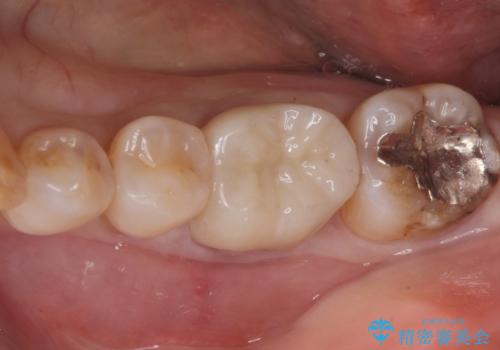

割れるリスクの少ないジルコニアクラウンにて治療しました。

- ジルコニアクラウン・仮歯 12.1万円費用は治療当時の料金となります

白い被せ物が入り、とても満足して頂けました。

現在銀の詰め物、被せ物のやりかえを検討しているそうです。